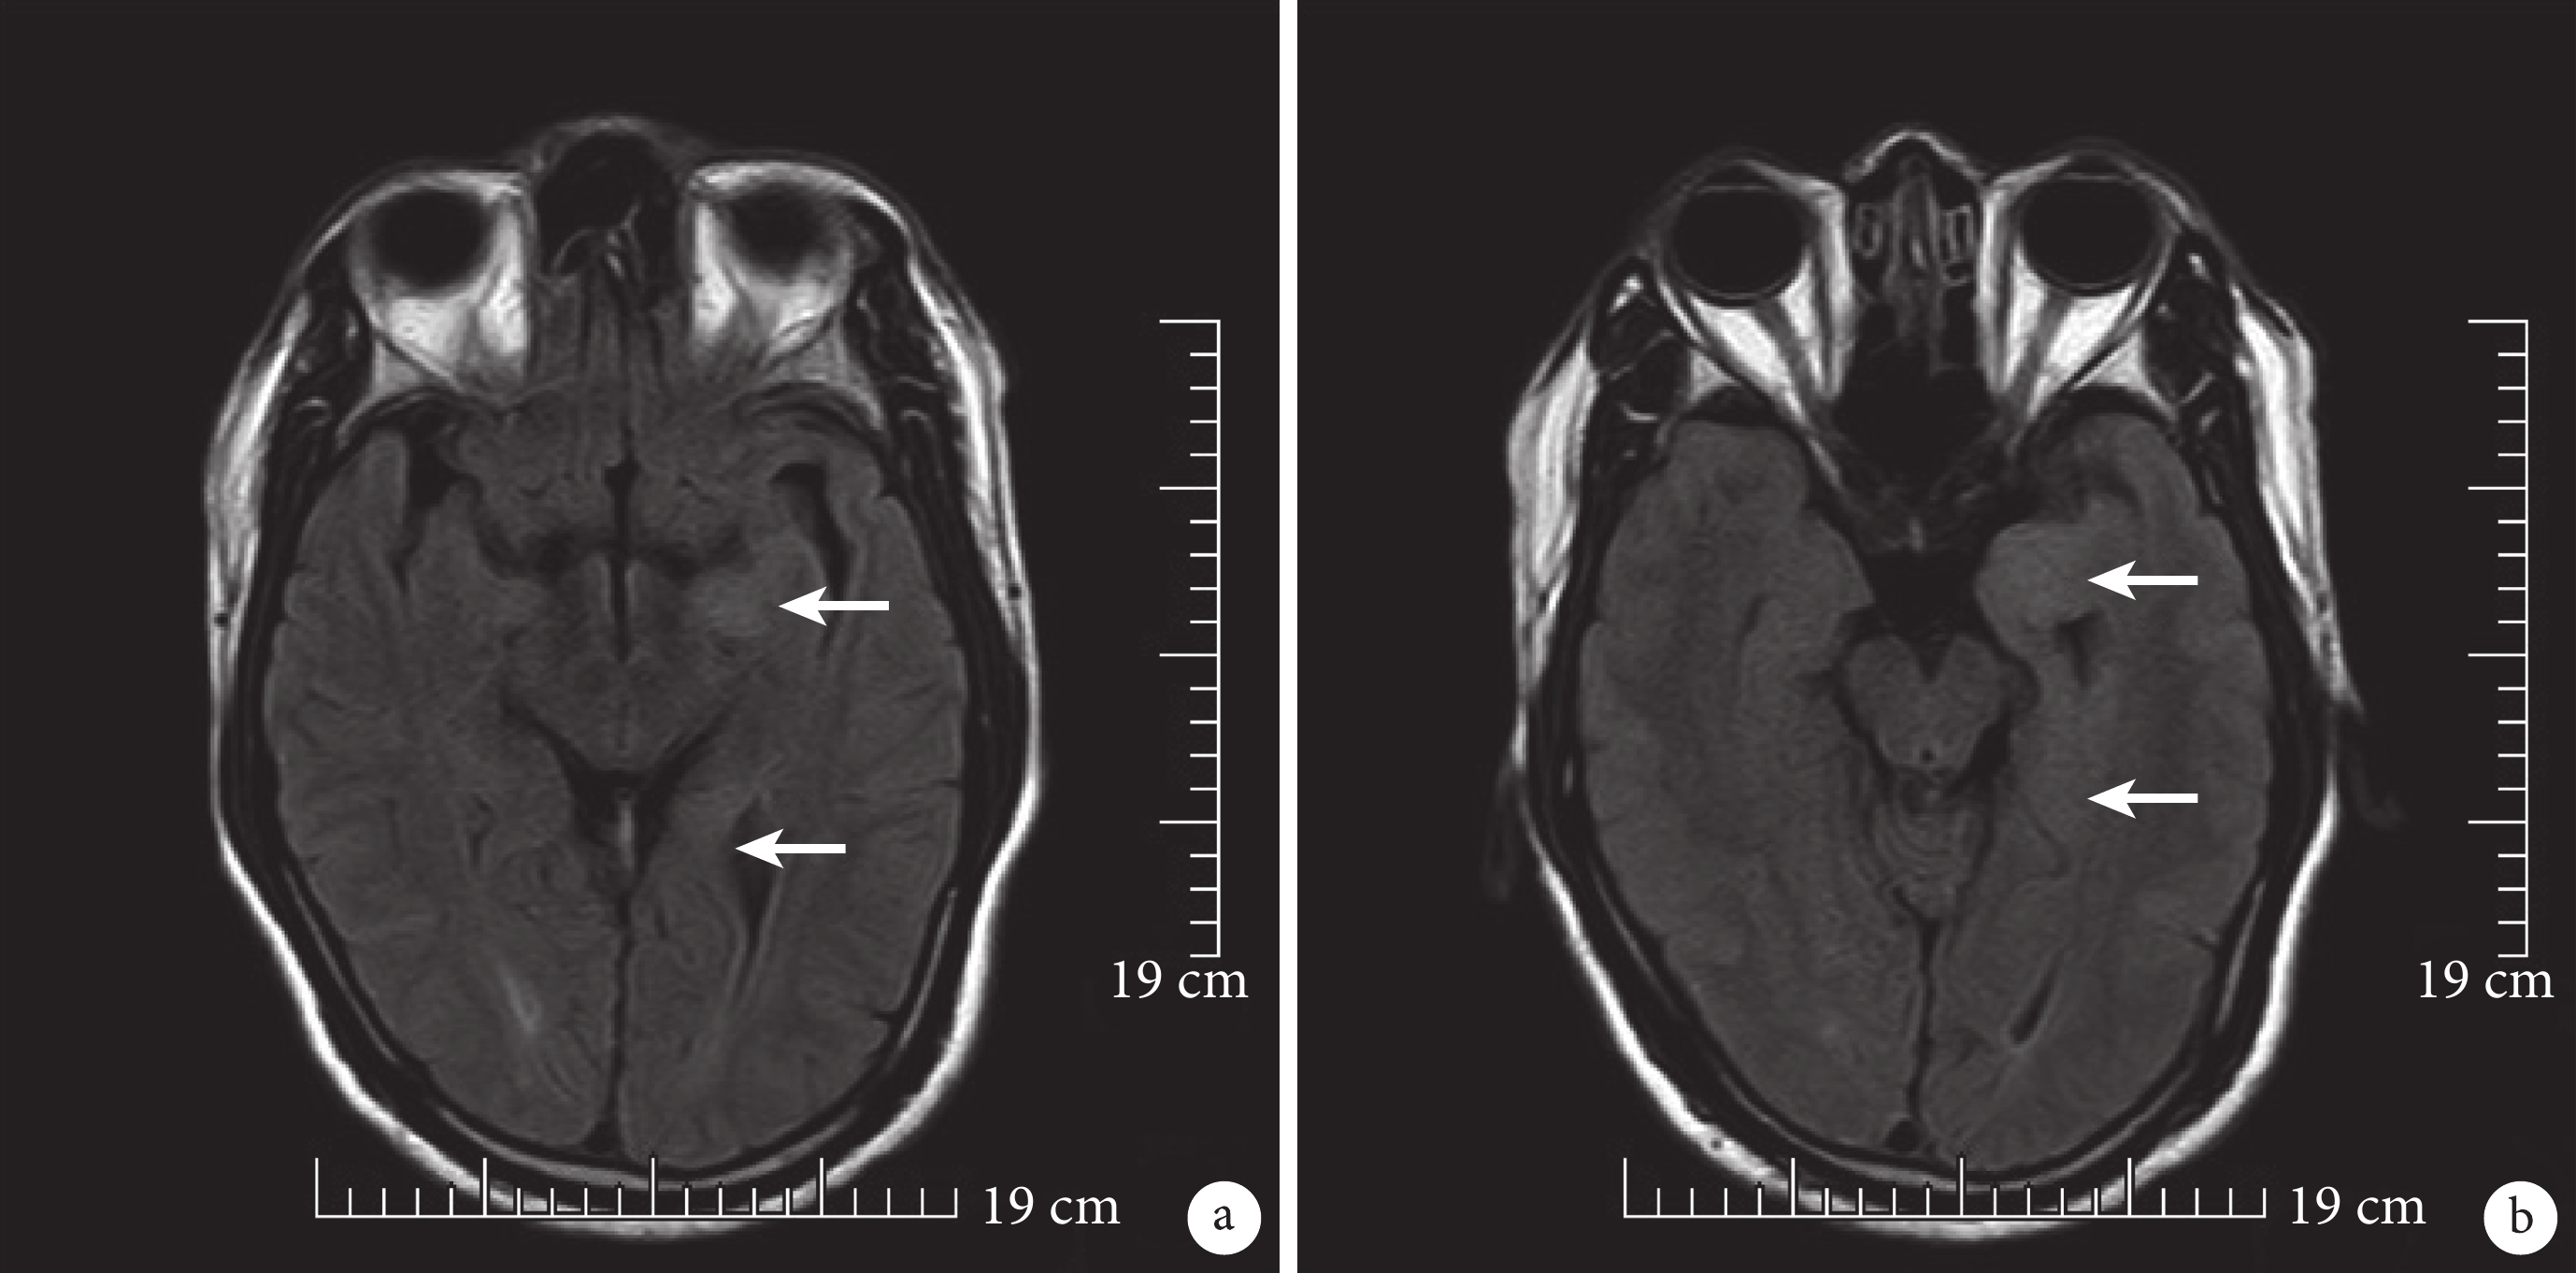

輔助檢查 入院完善相關檢查回示:① 三大常規、肝腎功、電解質、C-反應蛋白、凝血、風濕免疫全套未見異常;② 頭顱核磁共振+彌散+頭顱動脈成像(MRI+DWI+MRA)(圖 1a、b)示:1)FLAIR 見左側顳葉內側、海馬高信號,炎癥待排;2)顱內動脈主干未見異常;③ 腦脊液壓力:190 mm H2O;腦脊液免疫球蛋白:IgG:67.80 mg/L,IgA:8.67 mg/L,血清、腦脊液自身免疫性腦炎檢測 6 項:腦脊液抗 LGI1 抗體 IgG:陽性,1:1;血清抗 LGI1 抗體 IgG:陽性,1:30;腦脊液生化、細胞學、常規、真菌涂片、抗酸染色、細菌涂片、需厭氧培養、PCR、TORCH 未見明顯異常;④ 24 h 視頻腦電圖(VEEG)正常。

箭頭所指為 FLAIR 上見左側顳葉內側、海馬組織水腫、高信號。a. 為中腦層;b.為腦橋層

疾病早期顳葉內側 MRI FLAIR 高信號是診斷 LGI1 腦炎的重要證據[7, 8]。基底節和額葉皮層的 FLAIR 高信號也有報道[8]。有 24%的 FBDS 患者 EEG 檢測顯示局灶性減慢或癲癇樣變化[9]。LGI1 腦炎的診斷依賴于 LGI1 抗體,約 89%FBDS 患者的抗 LGI1 IgG 抗體陽性[5],且在血清中檢測到的這些抗體比在腦脊髓液中檢測具有更高的敏感性[2]。然而,腦脊液中高水平的抗 LGI1 抗體可能提示神經功能受損更嚴重[10]。本例患者頭部 MRI 提示左側顳葉內側海馬水腫以及高信號,血清和腦脊液中均檢測到抗 LGI1 IgG 抗體,且血清中抗體滴度高于腦脊液。這些結果均支持 LGI1 腦炎的診斷。此外,大多數 LGI1 腦炎患者是非副腫瘤的,據報道很少有患者患有惡性腫瘤,包括胸腺瘤或肺癌[11]。該例患者亦無腫瘤相關跡象。